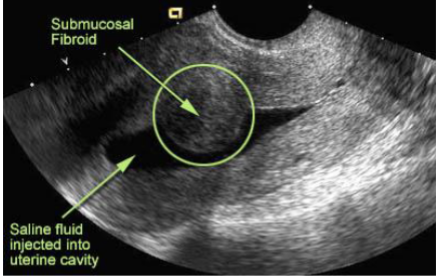

What is this and what type of scan

fibroids, transvaginal US